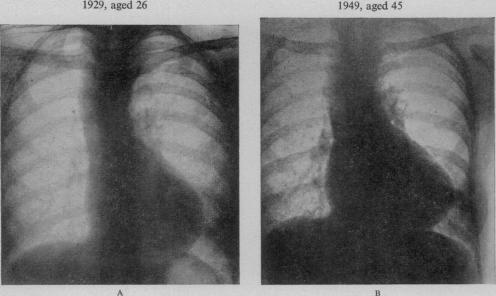

BEDFORD D E

Proc R Soc Med. 1956 Jun;49(6):314-6. doi: 10.1177/003591575604900602.